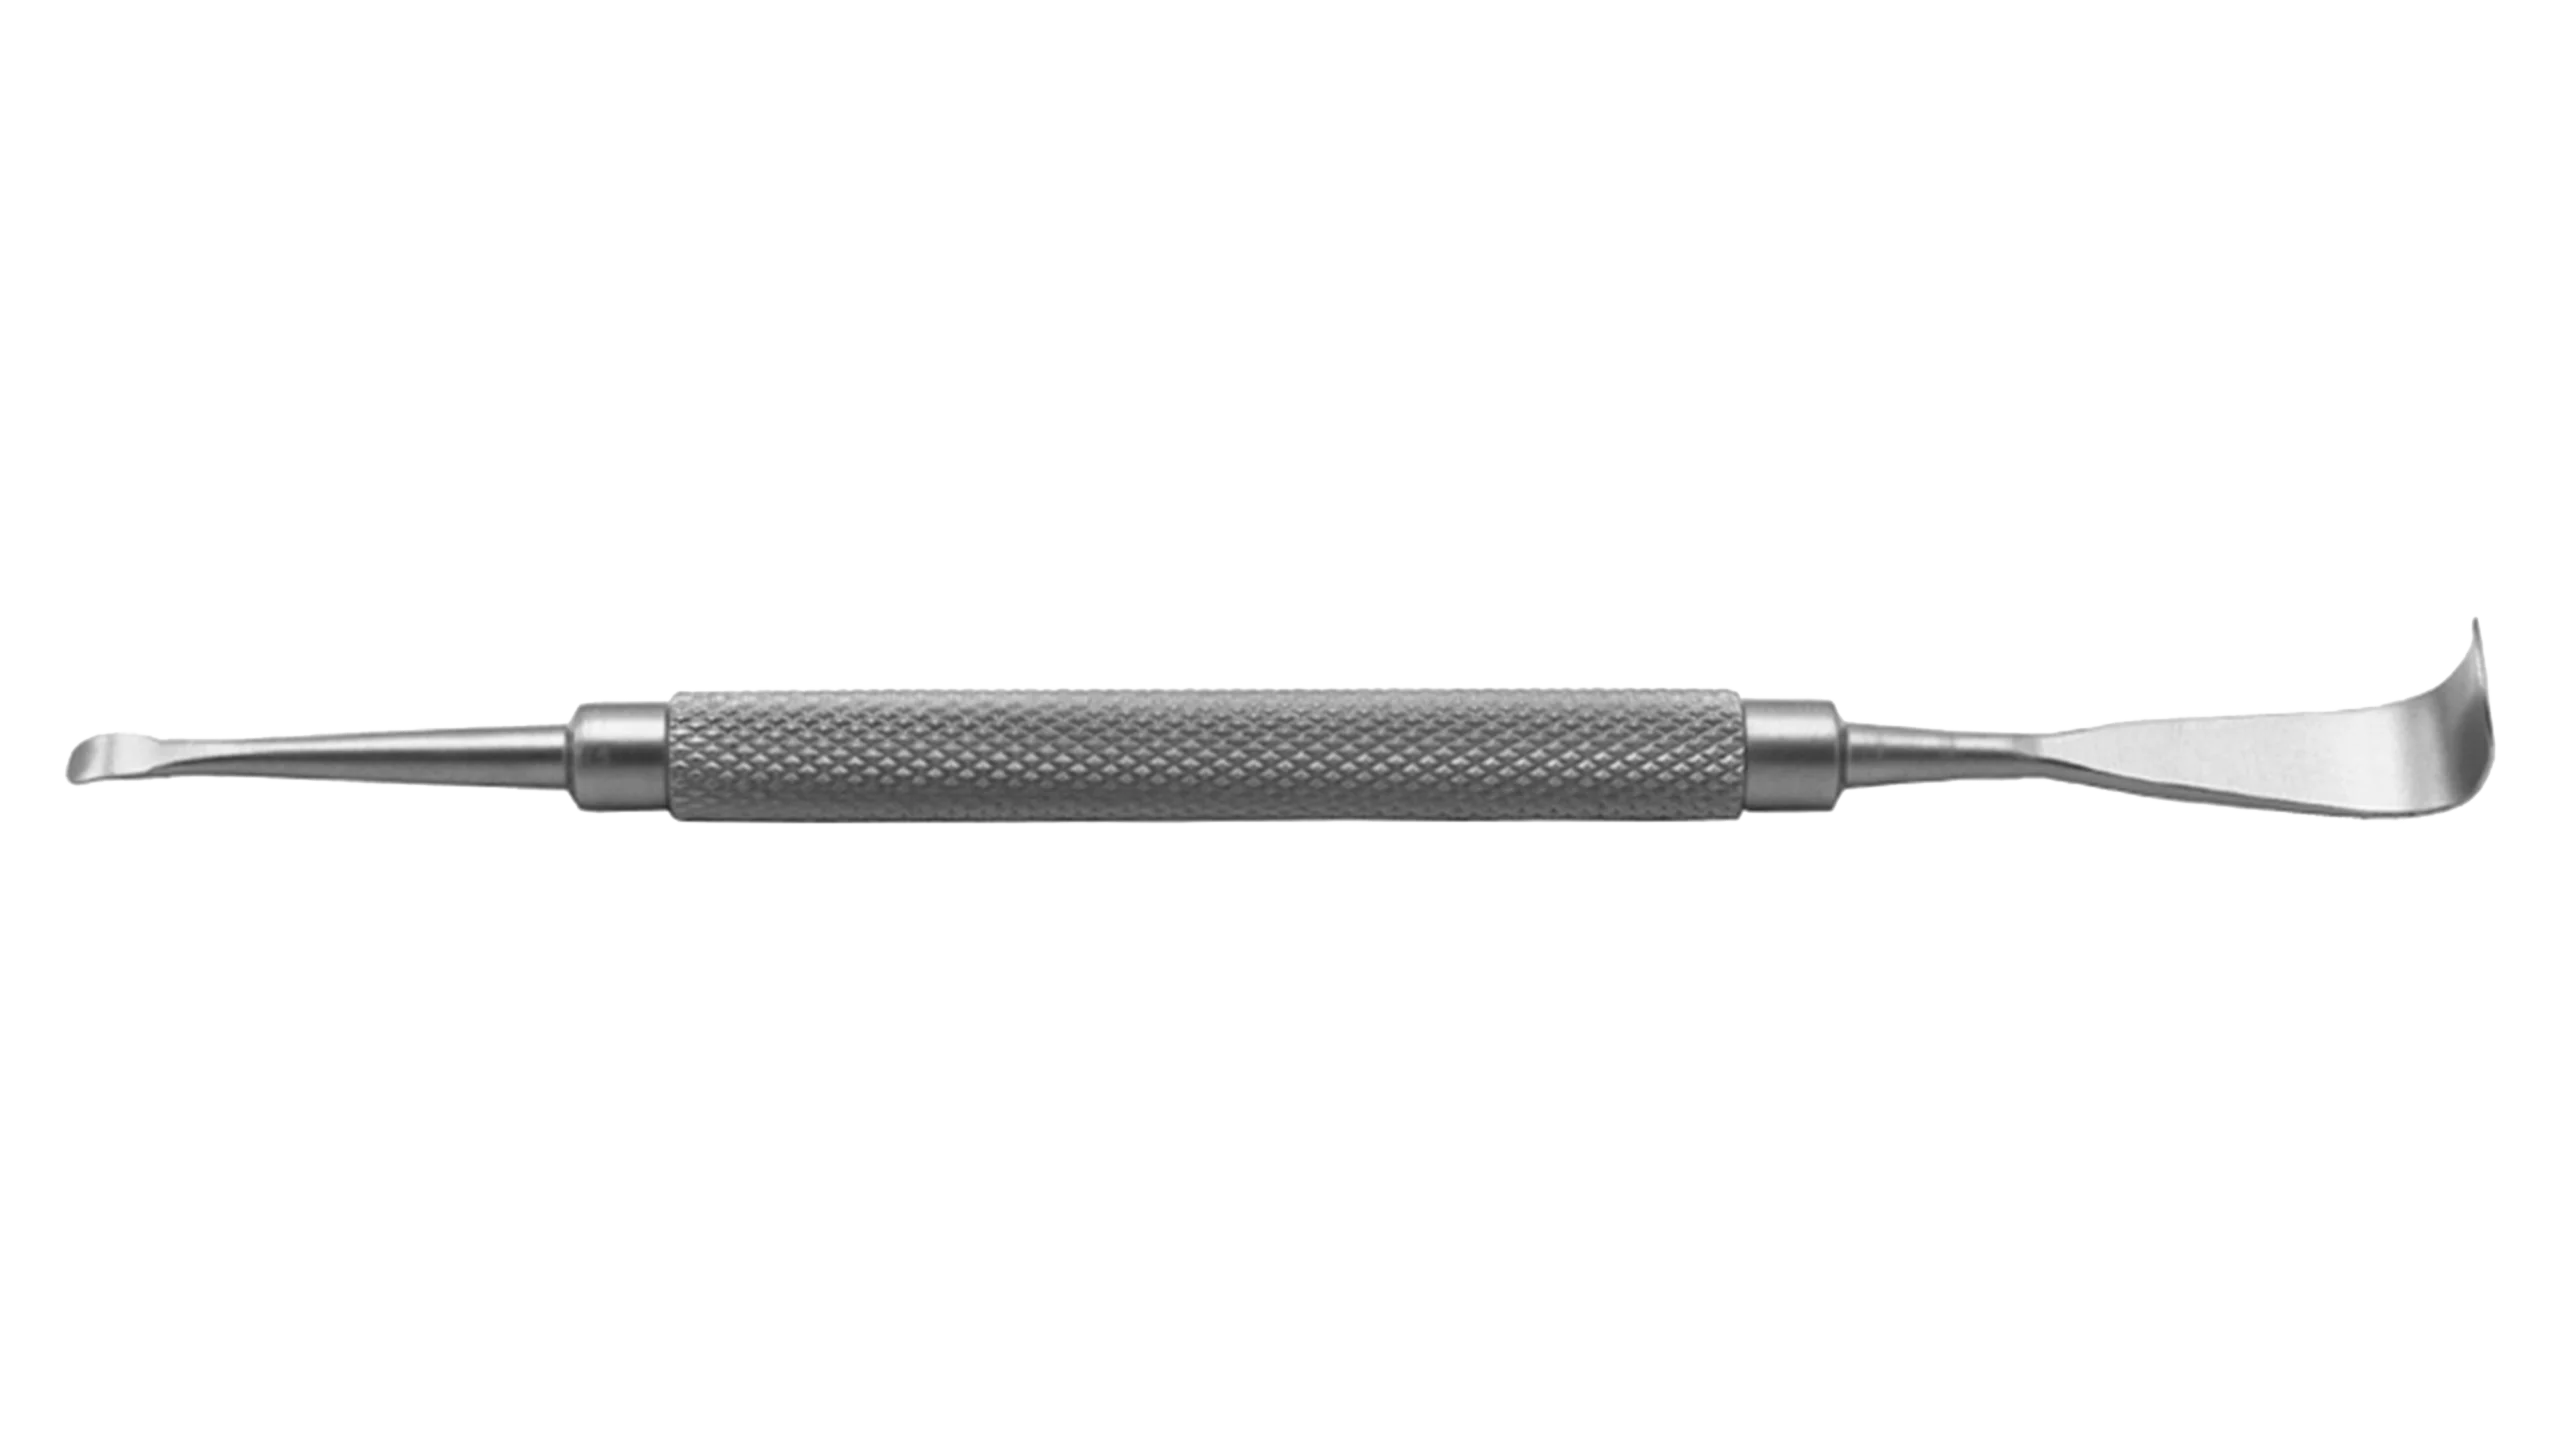

Ophthalmic Surgical Instruments

Wide range of recyclable ophthalmic surgery instruments.